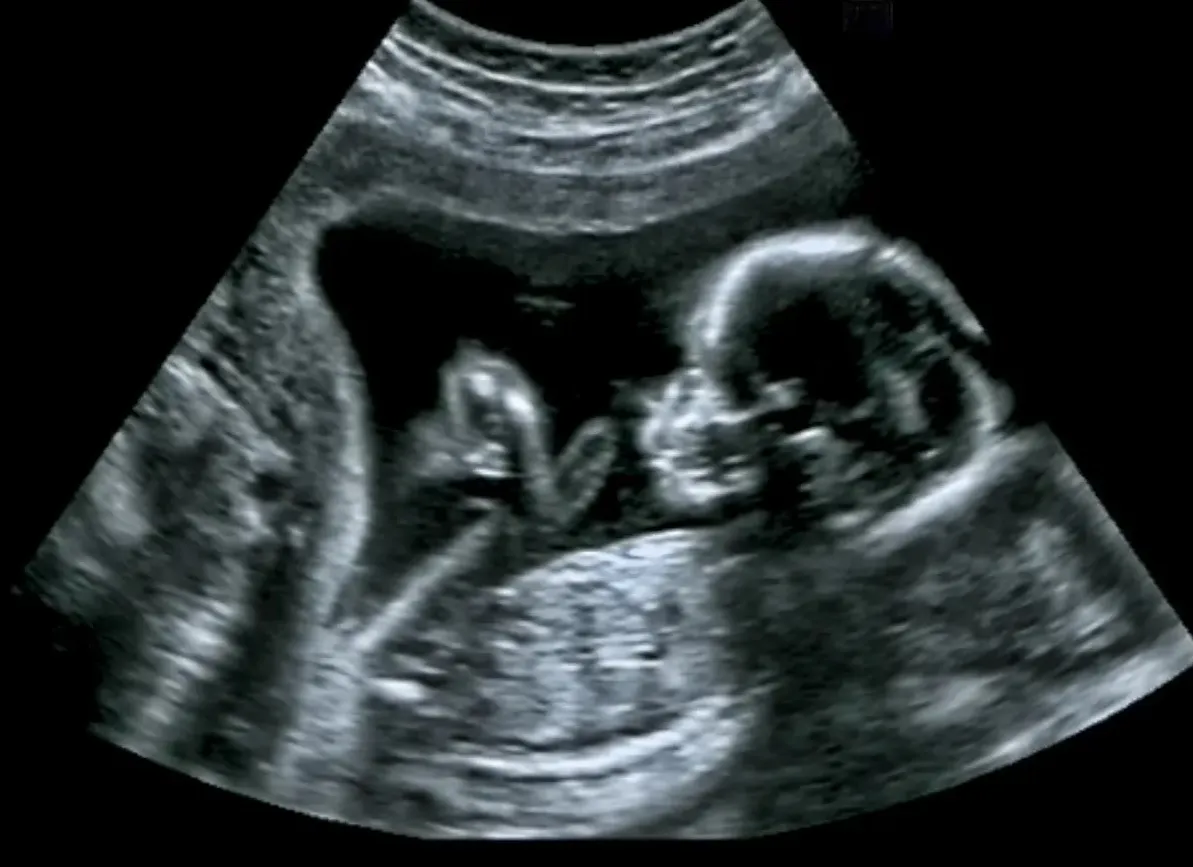

Во время редкой операции команде помог ориентироваться ультразвук.

Во время редкой операции команде помог ориентироваться ультразвук.© Shutterstock

Перед операцией матери ввели спинальную анестезию, а плод получил инъекцию анестетика, чтобы предотвратить его движение во время процедуры. Затем через матку ввели иглу, а ультразвуковое исследование помогло направить её на затылок ребёнка, где располагалась мальформация. После этого хирурги через катетер ввели в вену плода специальные металлические спирали, которые уменьшили количество крови, протекающей по вене.